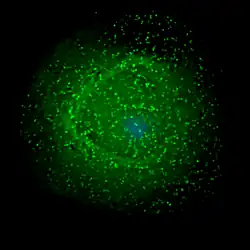

Assembly and release

HIV assembling on the surface of an infected macrophage. The HIV virions have been marked with a green fluorescent tag and then viewed under a fluorescent microscope.

The final step of the viral cycle, assembly of new HIV-1 virions, begins at the plasma membrane of the host cell. The Env polyprotein (gp160) goes through the endoplasmic reticulum and is transported to the Golgi apparatus where it is cleaved by furin resulting in the two HIV envelope glycoproteins, gp41 and gp120.[88] These are transported to the plasma membrane of the host cell where gp41 anchors gp120 to the membrane of the infected cell. The Gag (p55) and Gag-Pol (p160) polyproteins also associate with the inner surface of the plasma membrane along with the HIV genomic RNA as the forming virion begins to bud from the host cell. The budded virion is still immature as the gag polyproteins still need to be cleaved into the actual matrix, capsid and nucleocapsid proteins. This cleavage is mediated by the packaged viral protease and can be inhibited by antiretroviral drugs of the protease inhibitor class. The various structural components then assemble to produce a mature HIV virion.[89] Only mature virions are then able to infect another cell.